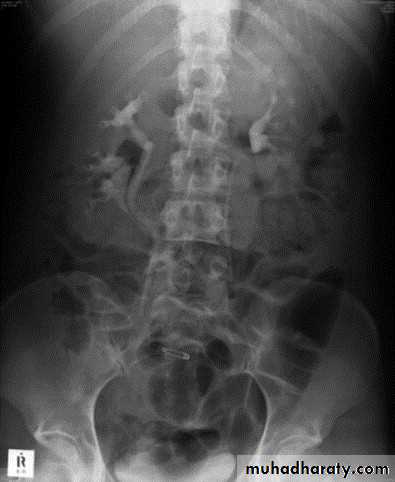

Horse shoe kidney -Kidneys may fail to separate.

-Almost invariably the lower poles remain fused.

-The kidneys axes are more parallel to the spine and malrotated.

-Diagnosis can be made by plain x-ray in some cases.

-US, CT scan and MRI can better demonstrate the anatomy and morphology hence the diagnosis.

-May be an incidental finding.

-PUJ obstruction and calculi formation are common .

IVU shows

1. The kidneys at low position .

2.Close to the spine with long axis parallel to the spine .

3. Malrotation manifested by medially directed calyces.

4- The renal pelvis and ureters are anterior and lateral in position .